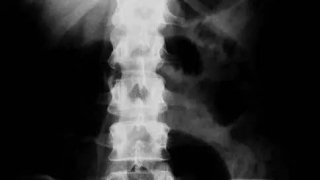

16 ฟิล์มเอ็กซเรย์ที่สยองและแปลกที่สุดในโลก

1. เอ็กซ์เรย์นี้แสดงให้เห็นลำไส้ในช่องท้องของผู้ป่วยมีส้อมสองอัน ปากกาลูกลื่น และแปรงสีฟัน 2. เอกซเรย์นี้ นิ้วกลางของชายชราคนนี้ถูกตะปูเจาะทะลุ 3. นี่คือภาพเอ็กซ์เรย์ที่เท้าของทหาร แสดงบาดแผลจากกระสุนปืน 4. X-ray สีนี้แสดงให้เห็นว่าเด็กชายอายุ 7 ขวบกลืนกุญแจเข้าไป 5. เจ้าของฟิล์มเอกซเรย์สีนี้มีช้อนและใบมีดอยู่ในลำไส้ของเขา 6. เจ้าของฟิล์มเอกซเรย์สีนี้มีเข็มกลัดอยู่ที่หลอดอาหาร 7. เจ้าของฟิล์มเอกซเ.. ดูเพิ่ม